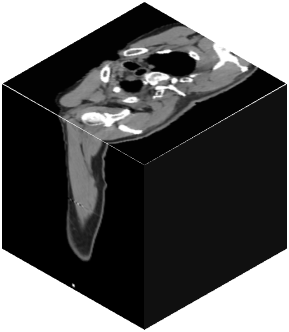

Vision transformers, with their ability to more efficiently model long-range context, have demonstrated impressive accuracy gains in several computer vision and medical image analysis tasks including segmentation. However, such methods need large labeled datasets for training, which is hard to obtain for medical image analysis. Self-supervised learning (SSL) has demonstrated success in medical image segmentation using convolutional networks. In this work, we developed a \underline{s}elf-distillation learning with \underline{m}asked \underline{i}mage modeling method to perform SSL for vision \underline{t}ransformers (SMIT) applied to 3D multi-organ segmentation from CT and MRI. Our contribution is a dense pixel-wise regression within masked patches called masked image prediction, which we combined with masked patch token distillation as pretext task to pre-train vision transformers. We show our approach is more accurate and requires fewer fine tuning datasets than other pretext tasks. Unlike prior medical image methods, which typically used image sets arising from disease sites and imaging modalities corresponding to the target tasks, we used 3,643 CT scans (602,708 images) arising from head and neck, lung, and kidney cancers as well as COVID-19 for pre-training and applied it to abdominal organs segmentation from MRI pancreatic cancer patients as well as publicly available 13 different abdominal organs segmentation from CT. Our method showed clear accuracy improvement (average DSC of 0.875 from MRI and 0.878 from CT) with reduced requirement for fine-tuning datasets over commonly used pretext tasks. Extensive comparisons against multiple current SSL methods were done. Code will be made available upon acceptance for publication.